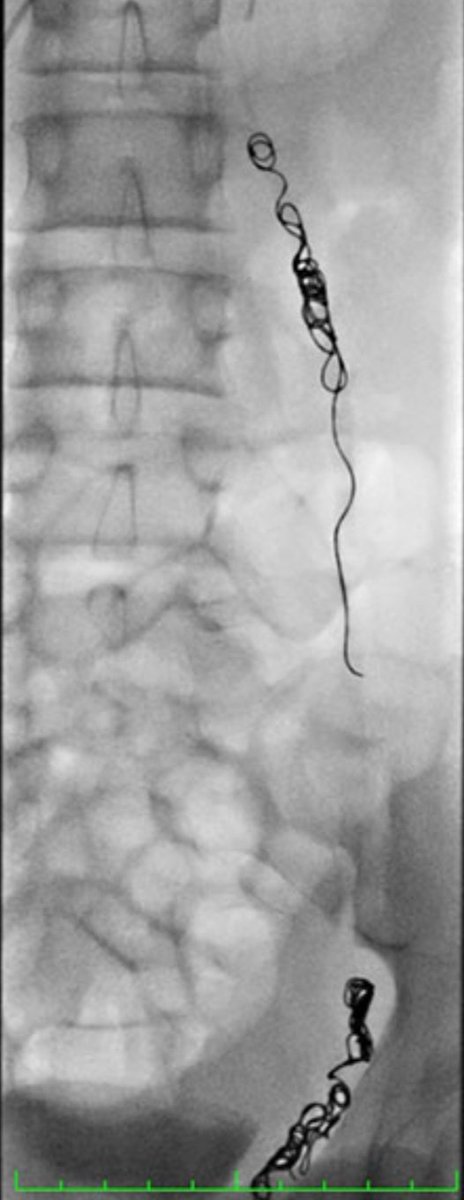

2️⃣أصلاح الدوالي بالاشعه التداخليه..

تعتبر طريقه جيده لازالة الدوالي خاصه في الاشخاص الذين يعانون من السمنه المفرطه وتتميز بسرعة الرجوع لممارسة الرياضه.

تختلف نسبة نجاح هذا الاجراء بحسب جهة الدوالي.